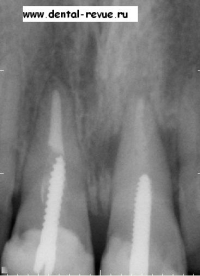

1. Прицельная рентгенограмма верхней челюсти (передние резцы) при первом обращении пациента (2004 год).

2. Прицельная рентгенограмма передних резцов верхней челюсти через 1,5 года: трещина корня 11, явный дефект костной ткани.